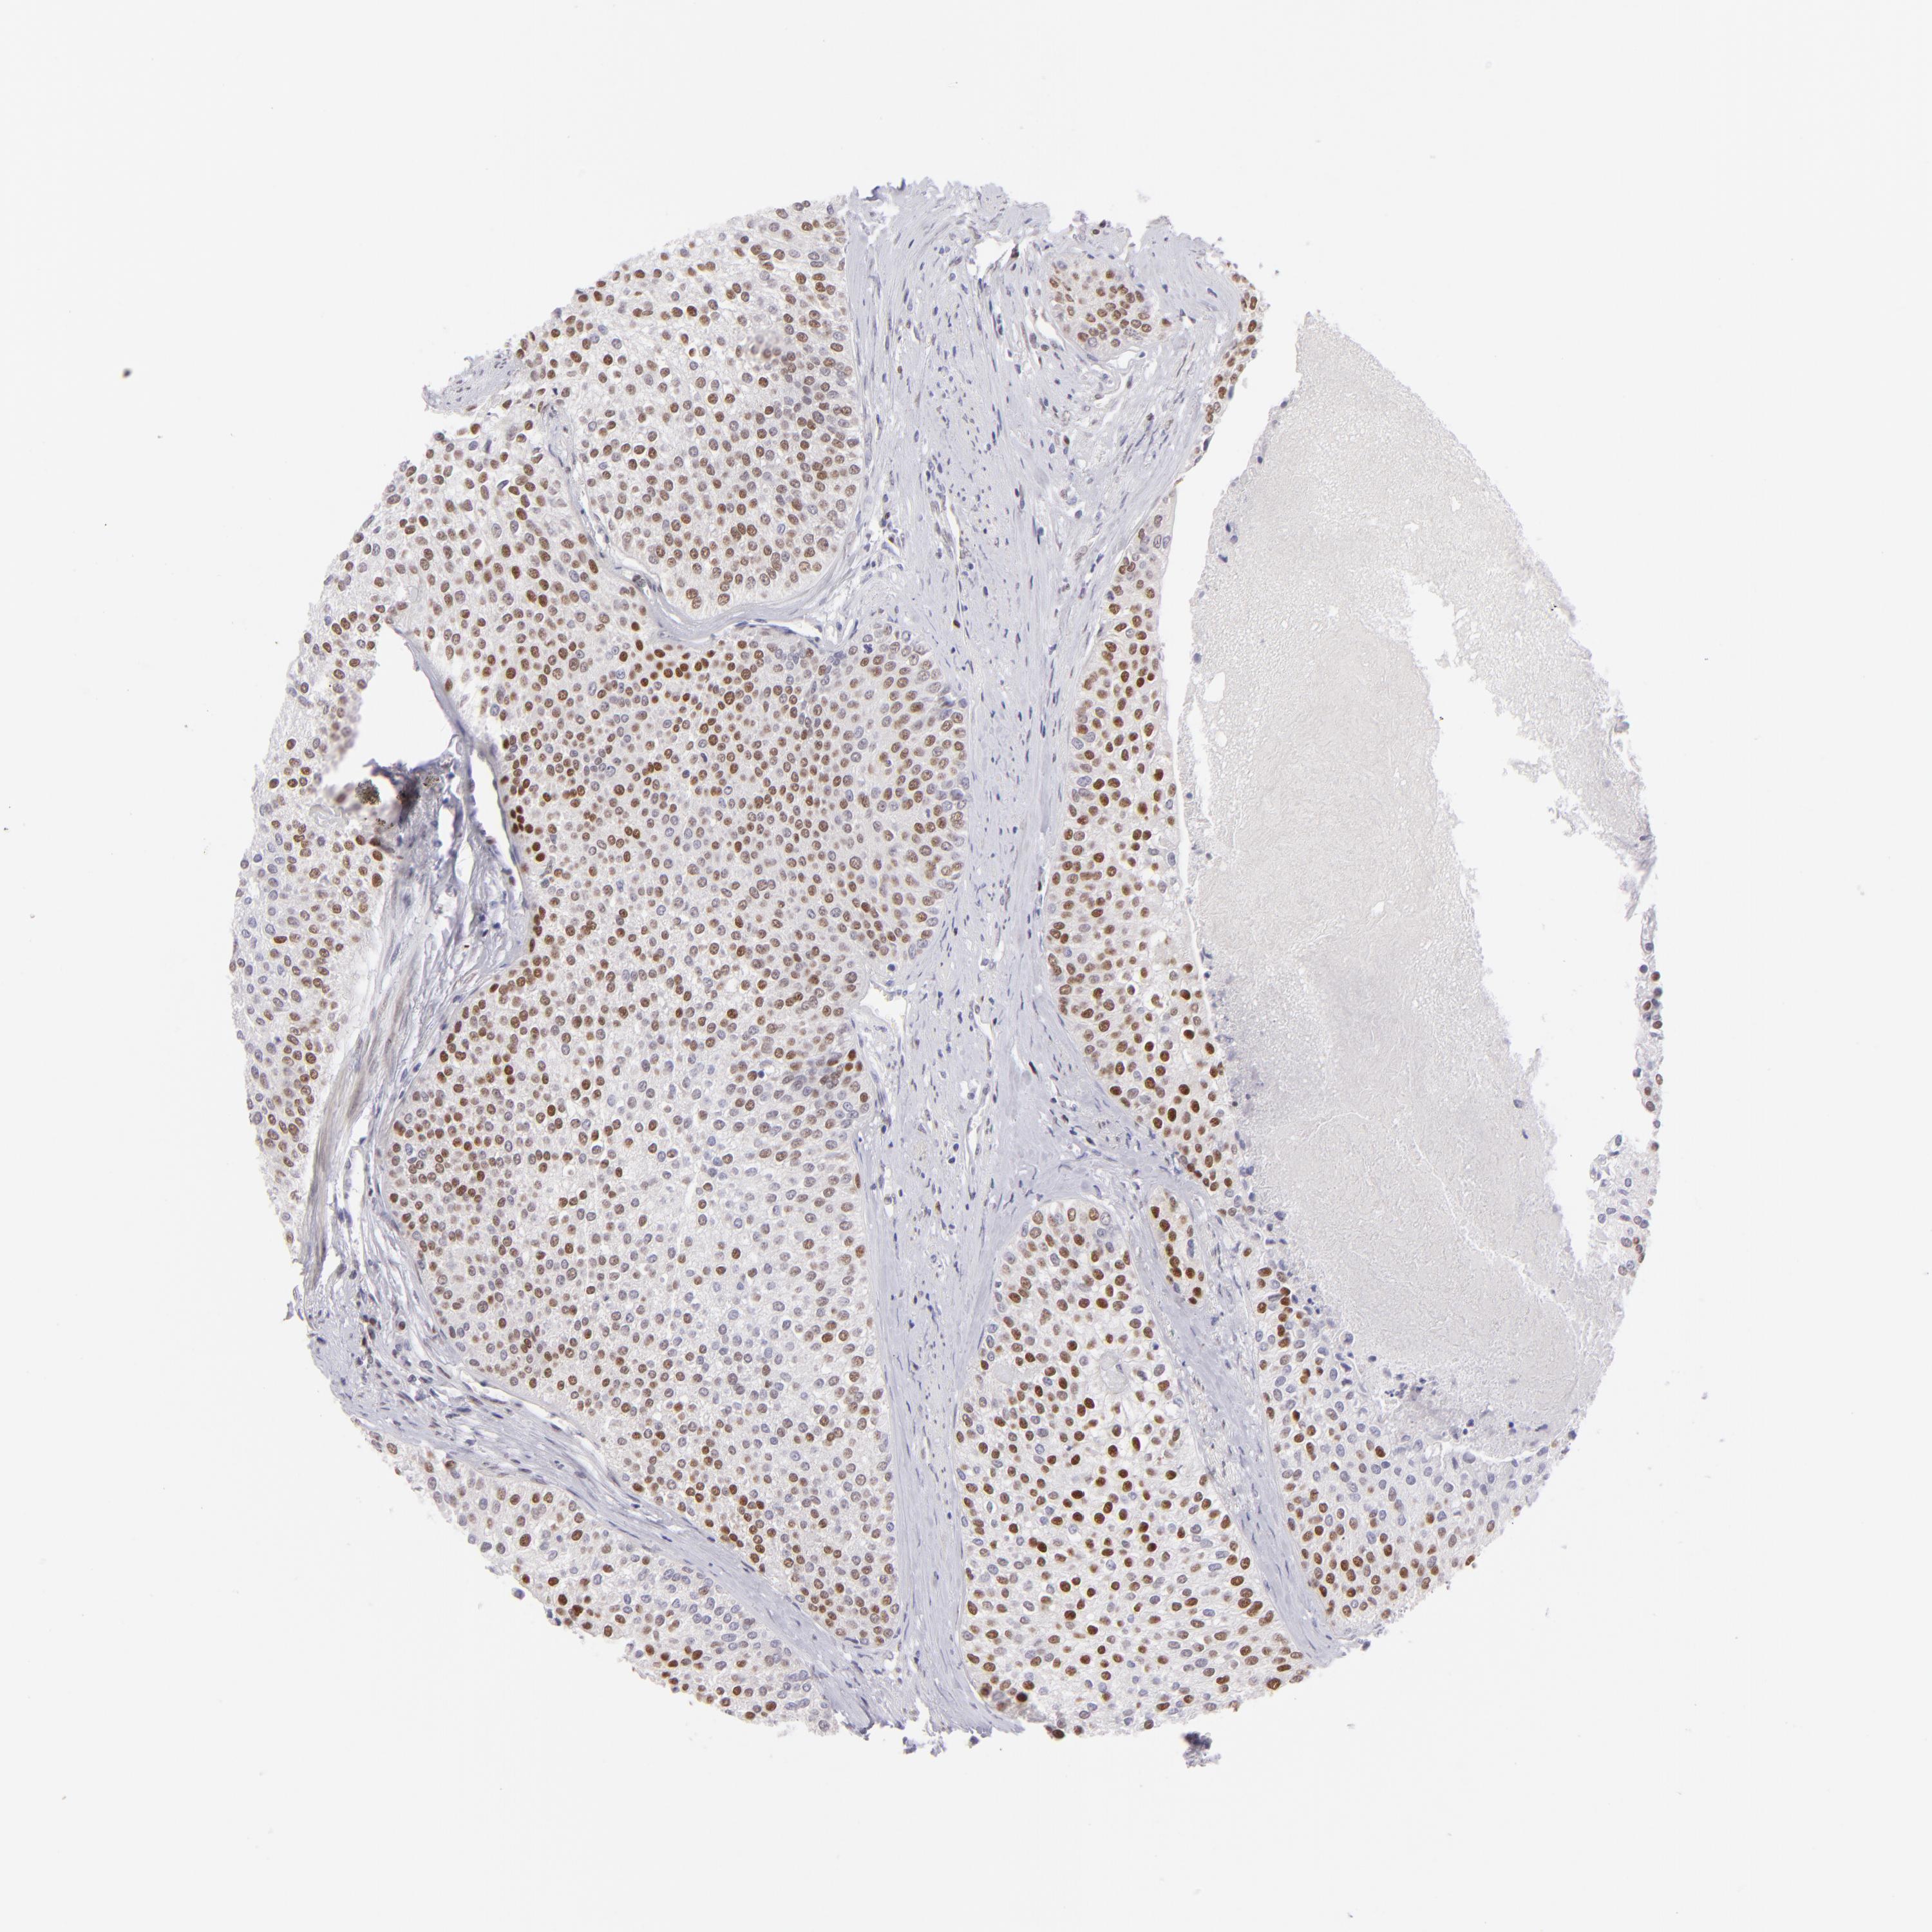

UROTHELIAL CANCER - Protein expressioni

A mouse-over function shows sample information and annotation data. Click on an image to view it in a full screen mode. Samples can be filtered based on level of antibody staining by selecting one or several of the following categories: high, medium, low and not detected. The assay and annotation is described here.

Note that samples used for immunohistochemistry by the Human Protein Atlas do not correspond to samples in the TCGA dataset.

Antibody stainingi

Antibody staining in the annotated cell types in the current human tissue is reported as not detected, low, medium, or high, based on conventional immunohistochemistry profiling in selected tissues. This score is based on the combination of the staining intensity and fraction of stained cells.

Each image is clickable and will lead to virtual microscopy that enables deeper exploration of all samples and also displays staining intensity scores, fraction scores and subcellular localization as well as patient and tissue information for each sample.

Antibody HPA064323

Antibody CAB002608

Urothelial carcinoma, High grade

Urothelial carcinoma, NOS

Urothelial carcinoma, Low grade

Adenocarcinoma, NOS